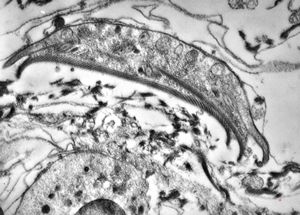

Borrelia Burgdorferi isolated from liquor